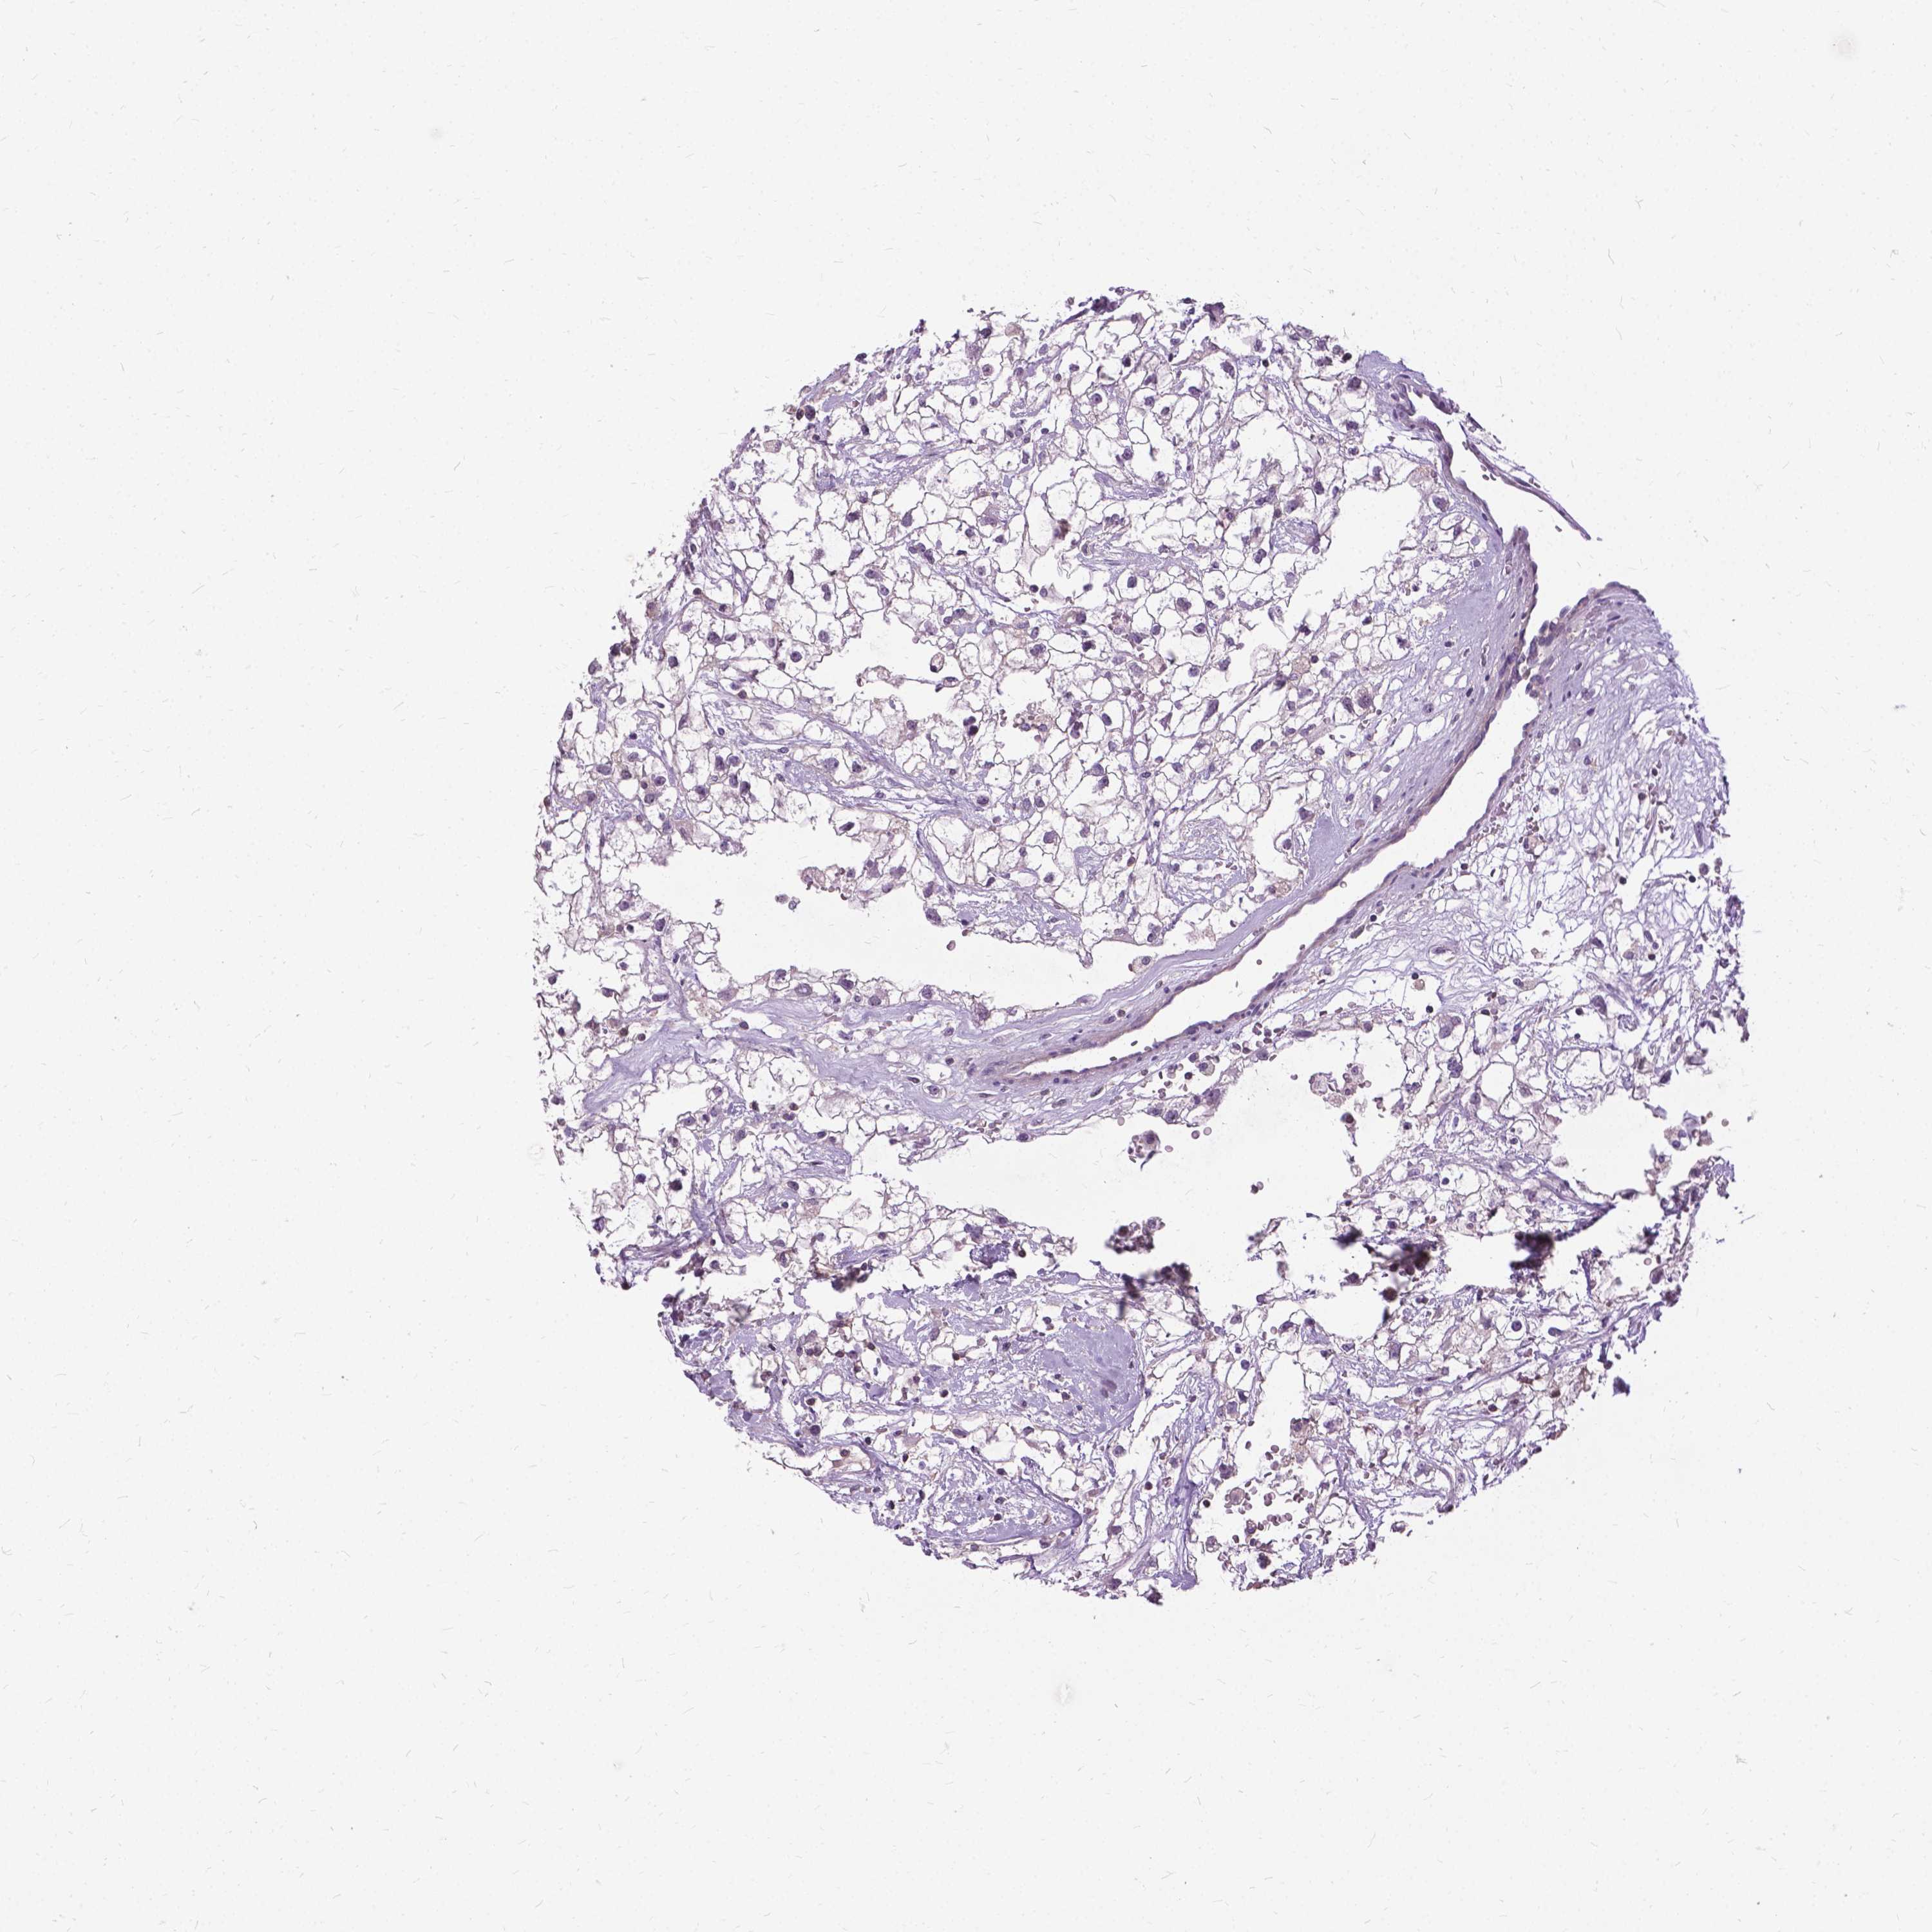

KIDNEY RENAL CLEAR CELL CARCINOMA (VALIDATION) - Interactive survival scatter ploti

The Survival Scatter plot shows the clinical status (i.e. dead or alive) for all individuals in the patient cohort, based on the same data that underlies the corresponding Kaplan-Meier plots. Patients that are alive at last time for follow-up are shown in blue and patients who have died during the study are shown in red.

The x-axis shows the expression levels (FPKM) of the investigated gene in the tumor tissue at the time of diagnosis. The y-axis shows the follow-up time after diagnosis (years). Both axes are complimented with kernel density curves demonstrating the data density over the axes. The top density plot shows the expression levels (FPKM) distribution among dead (red) and alive patients (blue). The right density plot shows the data density of the survived years of dead patients with high and low expression levels respectively, stratified using the cutoff indicated by the vertical dashed line through the Survival Scatter plot. This cutoff is automatically defined based on the FPKM cutoff that minimizes the p-score. The cutoff can be changed by dragging the vertical line or by entering a cutoff value in the square labeled "Current cut-off".

Under the Survival Scatter plot the p-score landscape (black curve; left axis) is shown together with dead median separation (red curve; right axis). Dead median separation is the difference in median mRNA expression between patients who have died with high and low expression, respectively. It is calculated as follows: median FPKM expression of dead patients with high expression - median FPKM expression of dead patients with low expression. This is intended to aid the user in visually exploring custom cutoffs and the associated p-scores and dead median separation.

Individual patient data is displayed and can be filtered by clicking on one or more of the category buttons on the top of the page. Categories describing expression level and patient information include: high, low, alive, dead, female, male and tumor stages. The scale of the x-axis can be toggled between linear and log-scale by clicking on the "x log" button. Mouse-over function shows TCGA ID, patient information and mRNA expression (FPKM) for each patient.

& Survival analysisi

Kaplan-Meier plots summarize results from analysis of correlation between mRNA expression level and patient survival. Patients were divided based on level of expression into one of the two groups "low" (under cut off) or "high" (over cut off). X-axis shows time for survival (years) and y-axis shows the probability of survival, where 1.0 corresponds to 100 percent.

JAK3 is not prognostic in Kidney Renal Clear Cell Carcinoma (validation)

Best expression cut offi

Based on the FPKM value of each gene, patients were classified into two groups and association between prognosis (survival) and gene expression (FPKM) was examined. The best expression cut-off refers the FPKM value that yields maximal difference with regard to survival between the two groups at the lowest log-rank P-value. Best expression cut-off was selected based on survival analysis .

When clicking on this number, the vertical dashed line indicating cut-off, the interactive survival plot, and the Kaplan-Meier curve will be adjusted to show results based on the best expression cut-off.

: 10.94

TCGA RNA samplesi

RNA-seq data is reported as average FPKM (number Fragments Per Kilobase of exon per Million reads), generated by the The Cancer Genome Atlas (TCGA) .

Normal distribution across the dataset is visualized with box plots, shown as median and 25th and 75th percentiles. Points are displayed as outliers if they are above or below 1.5 times the interquartile range. FPKM values of the individual samples are presented next to the box plot.

Average pTPM 9.6

Number of samples 100